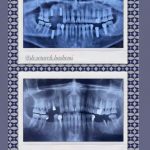

جراحی ایمپلنت های دندانی , پیوند استخوان , جراحی سینوس

در بعضی موارد مراجعه دیرهنگام فرد برای کاشت دندان (ایمپلنت) یا وجود کیست و تومورهای دهانی منجر به از بین رفتن فضای مناسب و کم شدن قطر و ارتفاع استخوان فک میشود که در این حالت، دندانپزشک قبل یا همزمان با جایگذاری فیکسچر، با استفاده از پودر و بلاک استخوانی و ممبرین (بایومتریالها) استخوان را بازسازی کرده تا شرایط مناسب برای قرارگیری ایمپلنت مهیا گردد. در این مواقع طول درمان بیمار (آماده شدن استخوان برای جایگذاری ایمپلنت) بسته به شرایط بیمار از ۳ تا ۶ ماه طول میکشد و دندانپزشک به کمک عکسهای رادیوگرافی میتواند روند درمان را دنبال کند و بهترین زمان را برای کاشت ایمپلنت تشخیص دهد.